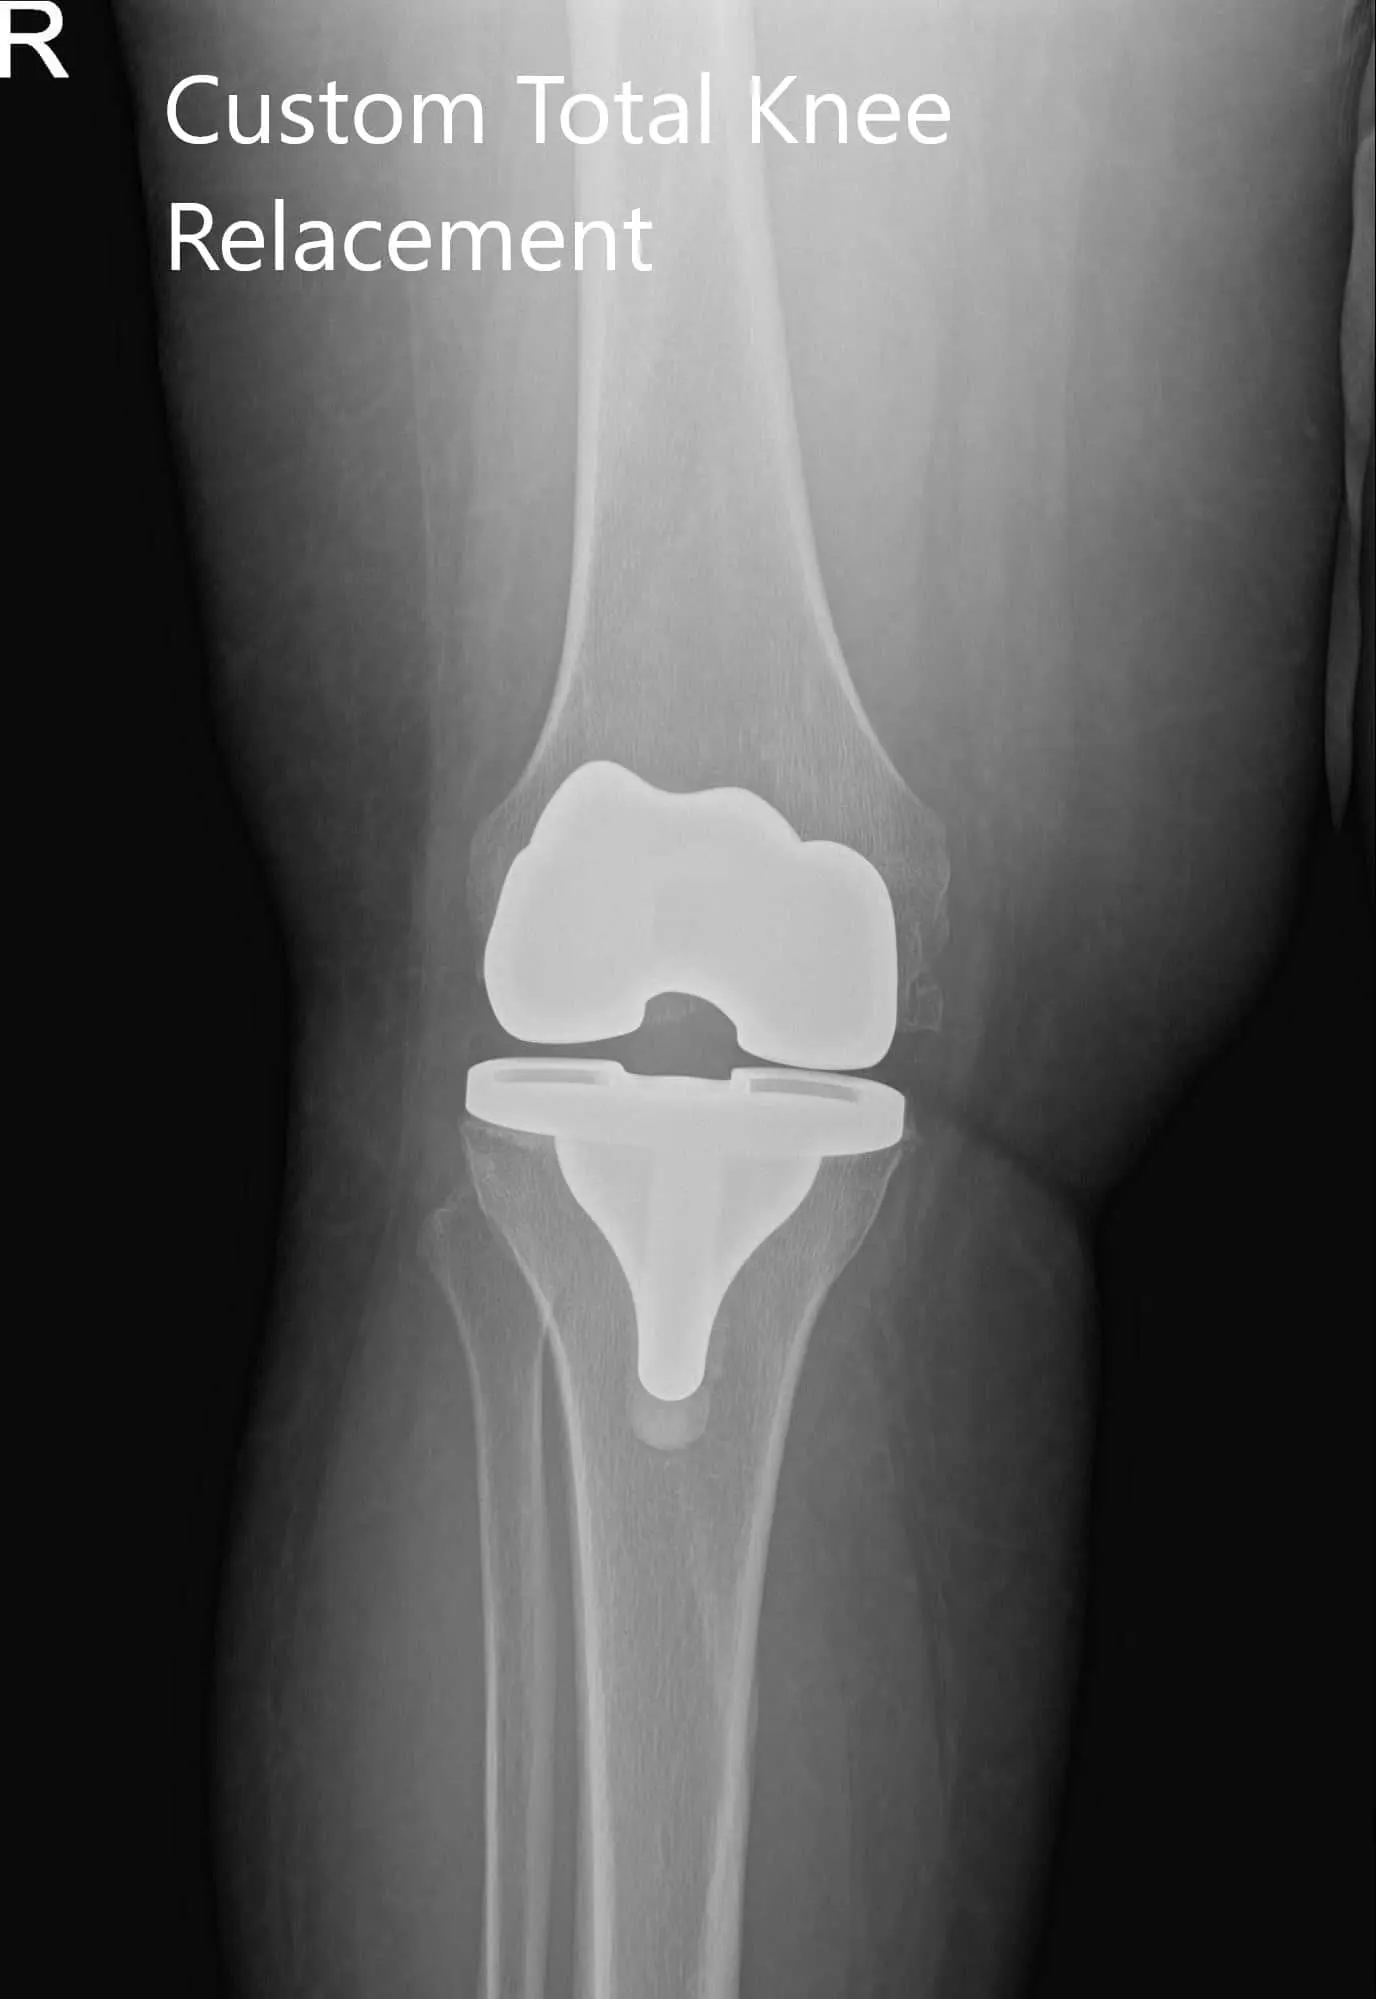

Postoperative X-ray of the patient’s right knee showing AP and lateral views

Implants used: 8 mm posterior stabilized polyethylene with tibial tray, femoral implant 32 mm,

6 mm thickness polyethylene with an 8 mm polyethylene insert.